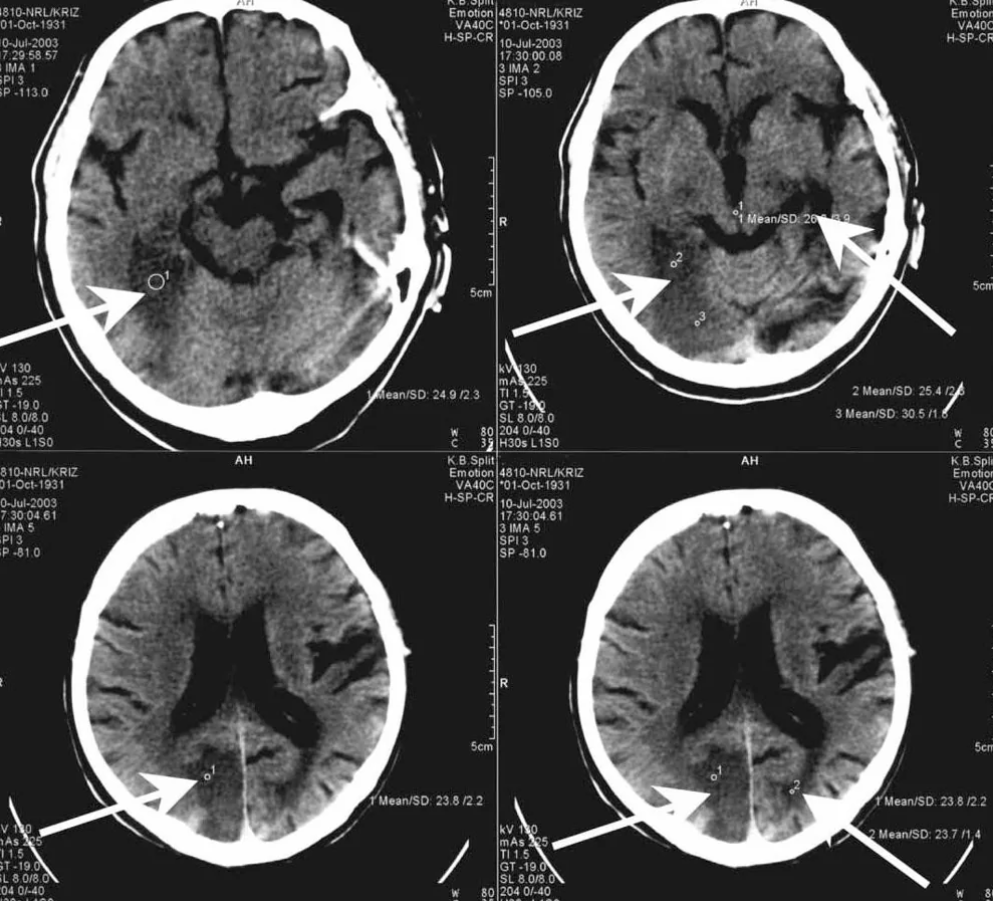

#7 Slepý muž, ktorý si myslí, že vidí

Anton-Babinského syndróm spôsobuje, že človek je úplne slepý, ale neuvedomuje si to. Je presvedčený, že vidí – hoci jeho mozog prestal spracúvať vizuálne informácie.